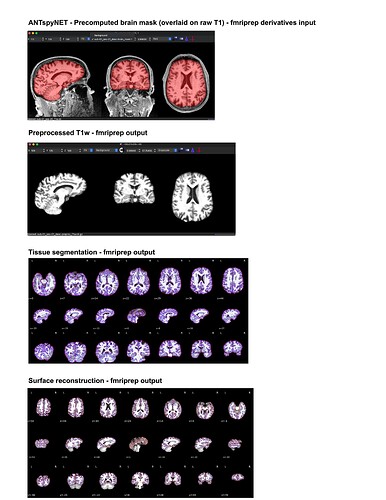

For my dataset I have found that ANTspyNET consistently produces a good/clean brain mask compared to fmriprep (antsBrainExtraction x Freesurfeer method). The default fmriprep method often outputs brain mask/segmentations that include the skull/non-brain tissues. As a result, I have been feeding my ANTspyNET mask as input via the --derivatives flag. While this works and the resulting outputs look good (see attached screenshots: decent tissue segmentations, good BOLD-T1 coreg etc), I noticed that the preprocessed anatomical T1 gets skull stripped in the process. Is this a sign of something going wrong under the hood?